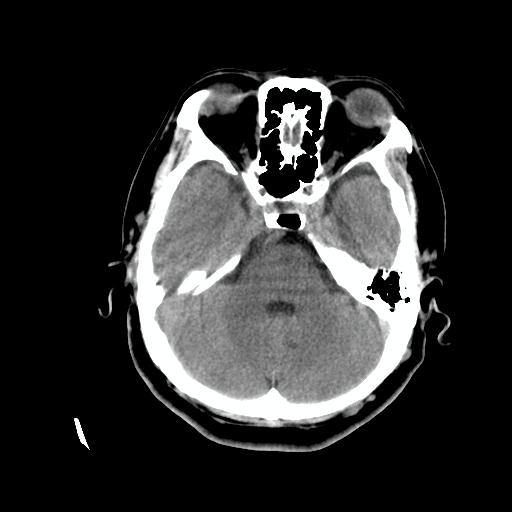

标题: CT24768:双侧脑室内囊性病变,主各位站友会诊。 [打印本页]

标题: CT24768:双侧脑室内囊性病变,主各位站友会诊。

患者女,62岁,临床提供头痛、头晕数月,无恶心及呕吐,近日加重。请各位站友看看,能否定为双侧脑室脉络丛囊肿,如果不能,应考虑什么?谢谢!

脉络丛囊肿属神经上皮性囊肿.好发于双侧脉络膜球,通常于影像检查或活检时偶然发现.患者无症状,病灶较小,双侧对称性,脑室膨胀轻.多数病灶在信号上与室管膜囊肿有所不同.在dwi上呈部分高信号,t2 flair上呈不均匀高信号.增强后呈结节状或环形增强

除了脉络膜丛囊肿外,枕叶内的片状钙化密度影,其周围无水肿,可能还要考虑血管畸形吧,建议增强扫描以明确诊断。